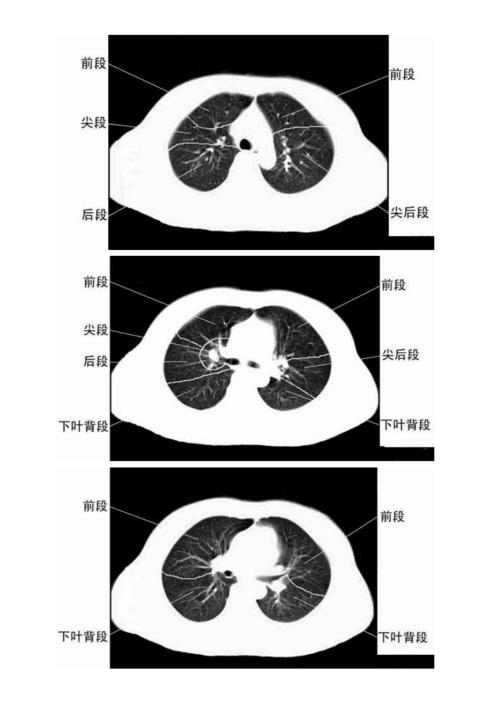

ct肺分叶分段解剖图,肺的分段分叶解剖图ct

ct肺的分叶分段

文档网 所有分类 医药卫生 临床医学 ct正常彩色解剖图-肺段 肺ct正常

胸部ct肺段划分口诀

肺部分段解剖